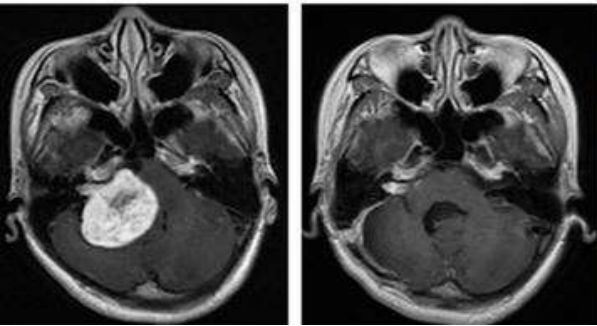

治疗期间,吴女士唾液分泌、皮肤、甲状腺无显著影响。治疗后MRI显示鼻咽左侧壁的局部复发已经明显缩小。两个月后吴女士开始正常上班。目前随访,病情处于稳定态势。